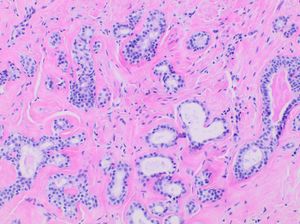

![사람의 [[턱밑샘]]. 오른쪽에는 점액 [[꽈리 (해부학)|꽈리]], 왼쪽에는 장액 꽈리 그룹이 있다.](https://cdn.onul.works/wiki/noimage.png)